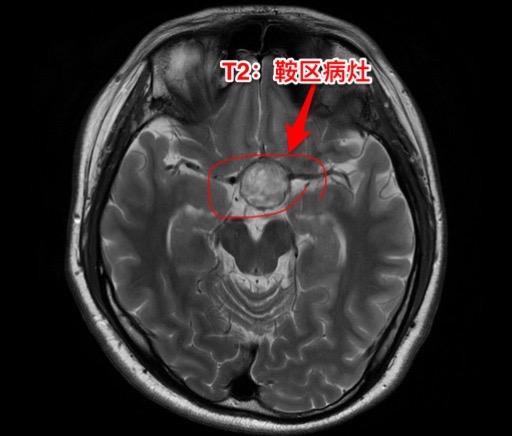

第一次经鼻手术后诊断为颅咽管瘤,可靠吗?27岁广西壮族自治区人,自幼视力不好。15个月前因多饮多尿、内分泌失调、视力下降在外院检查后诊断为颅咽管瘤,并作了经鼻内镜手术。取出一部分肿瘤内容物,病理报告为“角化物”。出院时诊断为“颅咽管瘤”。 一个月前患者又感视力下降,复查磁共振显示鞍区颅咽管瘤复发了,来找我作手术。头CT和磁共振见图。DWi显示肿瘤内容物呈白色,弥散受限,说明这不是颅咽管瘤。 手术中(我们采用开颅手术)看见肿瘤内容物为脱落角化上皮,其中未见毛发。将病灶囊皮及内